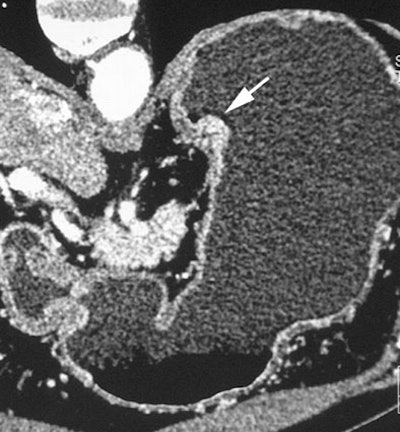

| Early gastric cancers. A 69-year-old man with protruding type of early gastric cancer. Oblique multiplanar reconstruction perpendicular to gastric wall shows protruding mass (arrow) of gastric cardia. Fig. 2A, Shimizu K, Ito K, Matsunaga N, Shimizu A, Kawakami Y. "Diagnosis of Gastric Cancer with MDCT Using the Water-Filling Method and Multiplanar Reconstruction: CT-Histologic Correlation" (AJR 2005; 185:1152-1158). |

The results were well-correlated with pathologic findings, and the overall accuracy of CT staging was 85%, they noted. On histology a high-attenuating abnormal inner layer corresponded to close proliferation of cancer cells, mainly mucosal and submucosal, whereas low-attenuating areas were indicative of scattered cancer cell diffusion such as in the proper muscle with dermoplastic changes and inflammatory reaction.

"In our seven early gastric cancers detected at MPR but not visible on 5-mm-slice axial images, six were located at the large or lesser curvature of the gastric angle or antrum," the group wrote. "Detection of early gastric cancers with 5-mm-slice axial images may be difficult because of partial volume artifacts where the gastric wall is tangent to the axial scan, such as the greater or lesser curvature of the gastric antrum or angle."

The overall detection rate for gastric cancers was 65%, including 96.2% (25/26) advanced cancers (pT2-pT4) and 41.2% (14/34) early cancers, the team reported. There was a statistically significant difference (p < 0.05) in the detection rate of early cancers between thin-slice MPR images and 5-mm axial slice images, but not between 5-mm axial images and 5-mm MPR images.

"In 34 early gastric cancers, thin-sliced MPR images depicted 68.8% of submucosal cancers ... and they showed 16.7% (3/18) of less invasive mucosal cancers," the researchers wrote. "The detection rate for grossly nonprotruding early cancers was comparatively low (28.6%)."